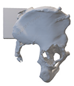

After smoothing the mask to remove surface roughness due to the low resolution of the diagnostic imaging, the hemi-pelvis with significant bone defect was printed using a Stratasys F270 (Stratasys Ltd., Rehovot, Israel) fused deposition modeling (FDM) 3D printer. A square grip was attached at the sacrum in such a way that the model could be exposed on a stand and used as a reference to facilitate the spatial orientation in the OR.

Therefore, the aiming device was first validated on a virtual 3D model. The entry and exit points and the path it takes through the bone were clearly visible in the design software, using the semi-transparent display mode. Then, the 3D-printed targeting model was fitted to the previously printed hemipelvis with its actual dimensions. The accuracy of the aiming was also verified by test drilling. The assembled model was then available to the surgeon in the OR for visual inspection, which helped to ensure spatial orientation (Figure 3).

Figure 3.

The 3D-printed hemipelvis with the aiming device in the OR.